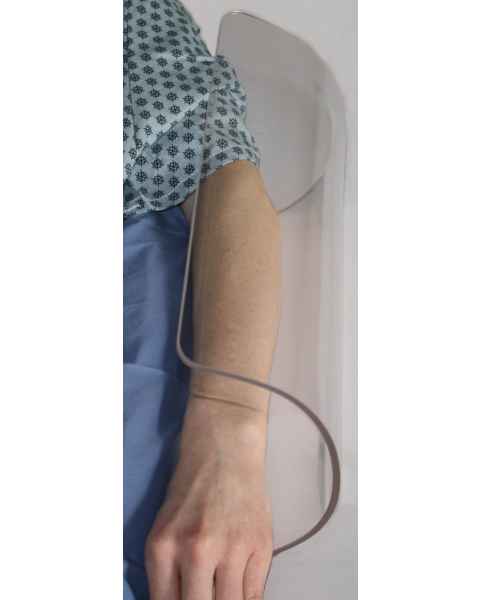

Arm Guards

Even the most skilled physician needs high-quality surgical accessories to help ensure an ergonomic working environment and to provide the patient with the highest possible level of comfort. Our surgical arm guards are designed to prevent procedure-related nerve damage, muscle tension, and skin irritation when the patient is in a prone or supine position. With a surgical arm shield in place, the doctor's weight will rest on the guard instead of against the patient's arm, which can cause patient injury and interfere with anesthesia lines.